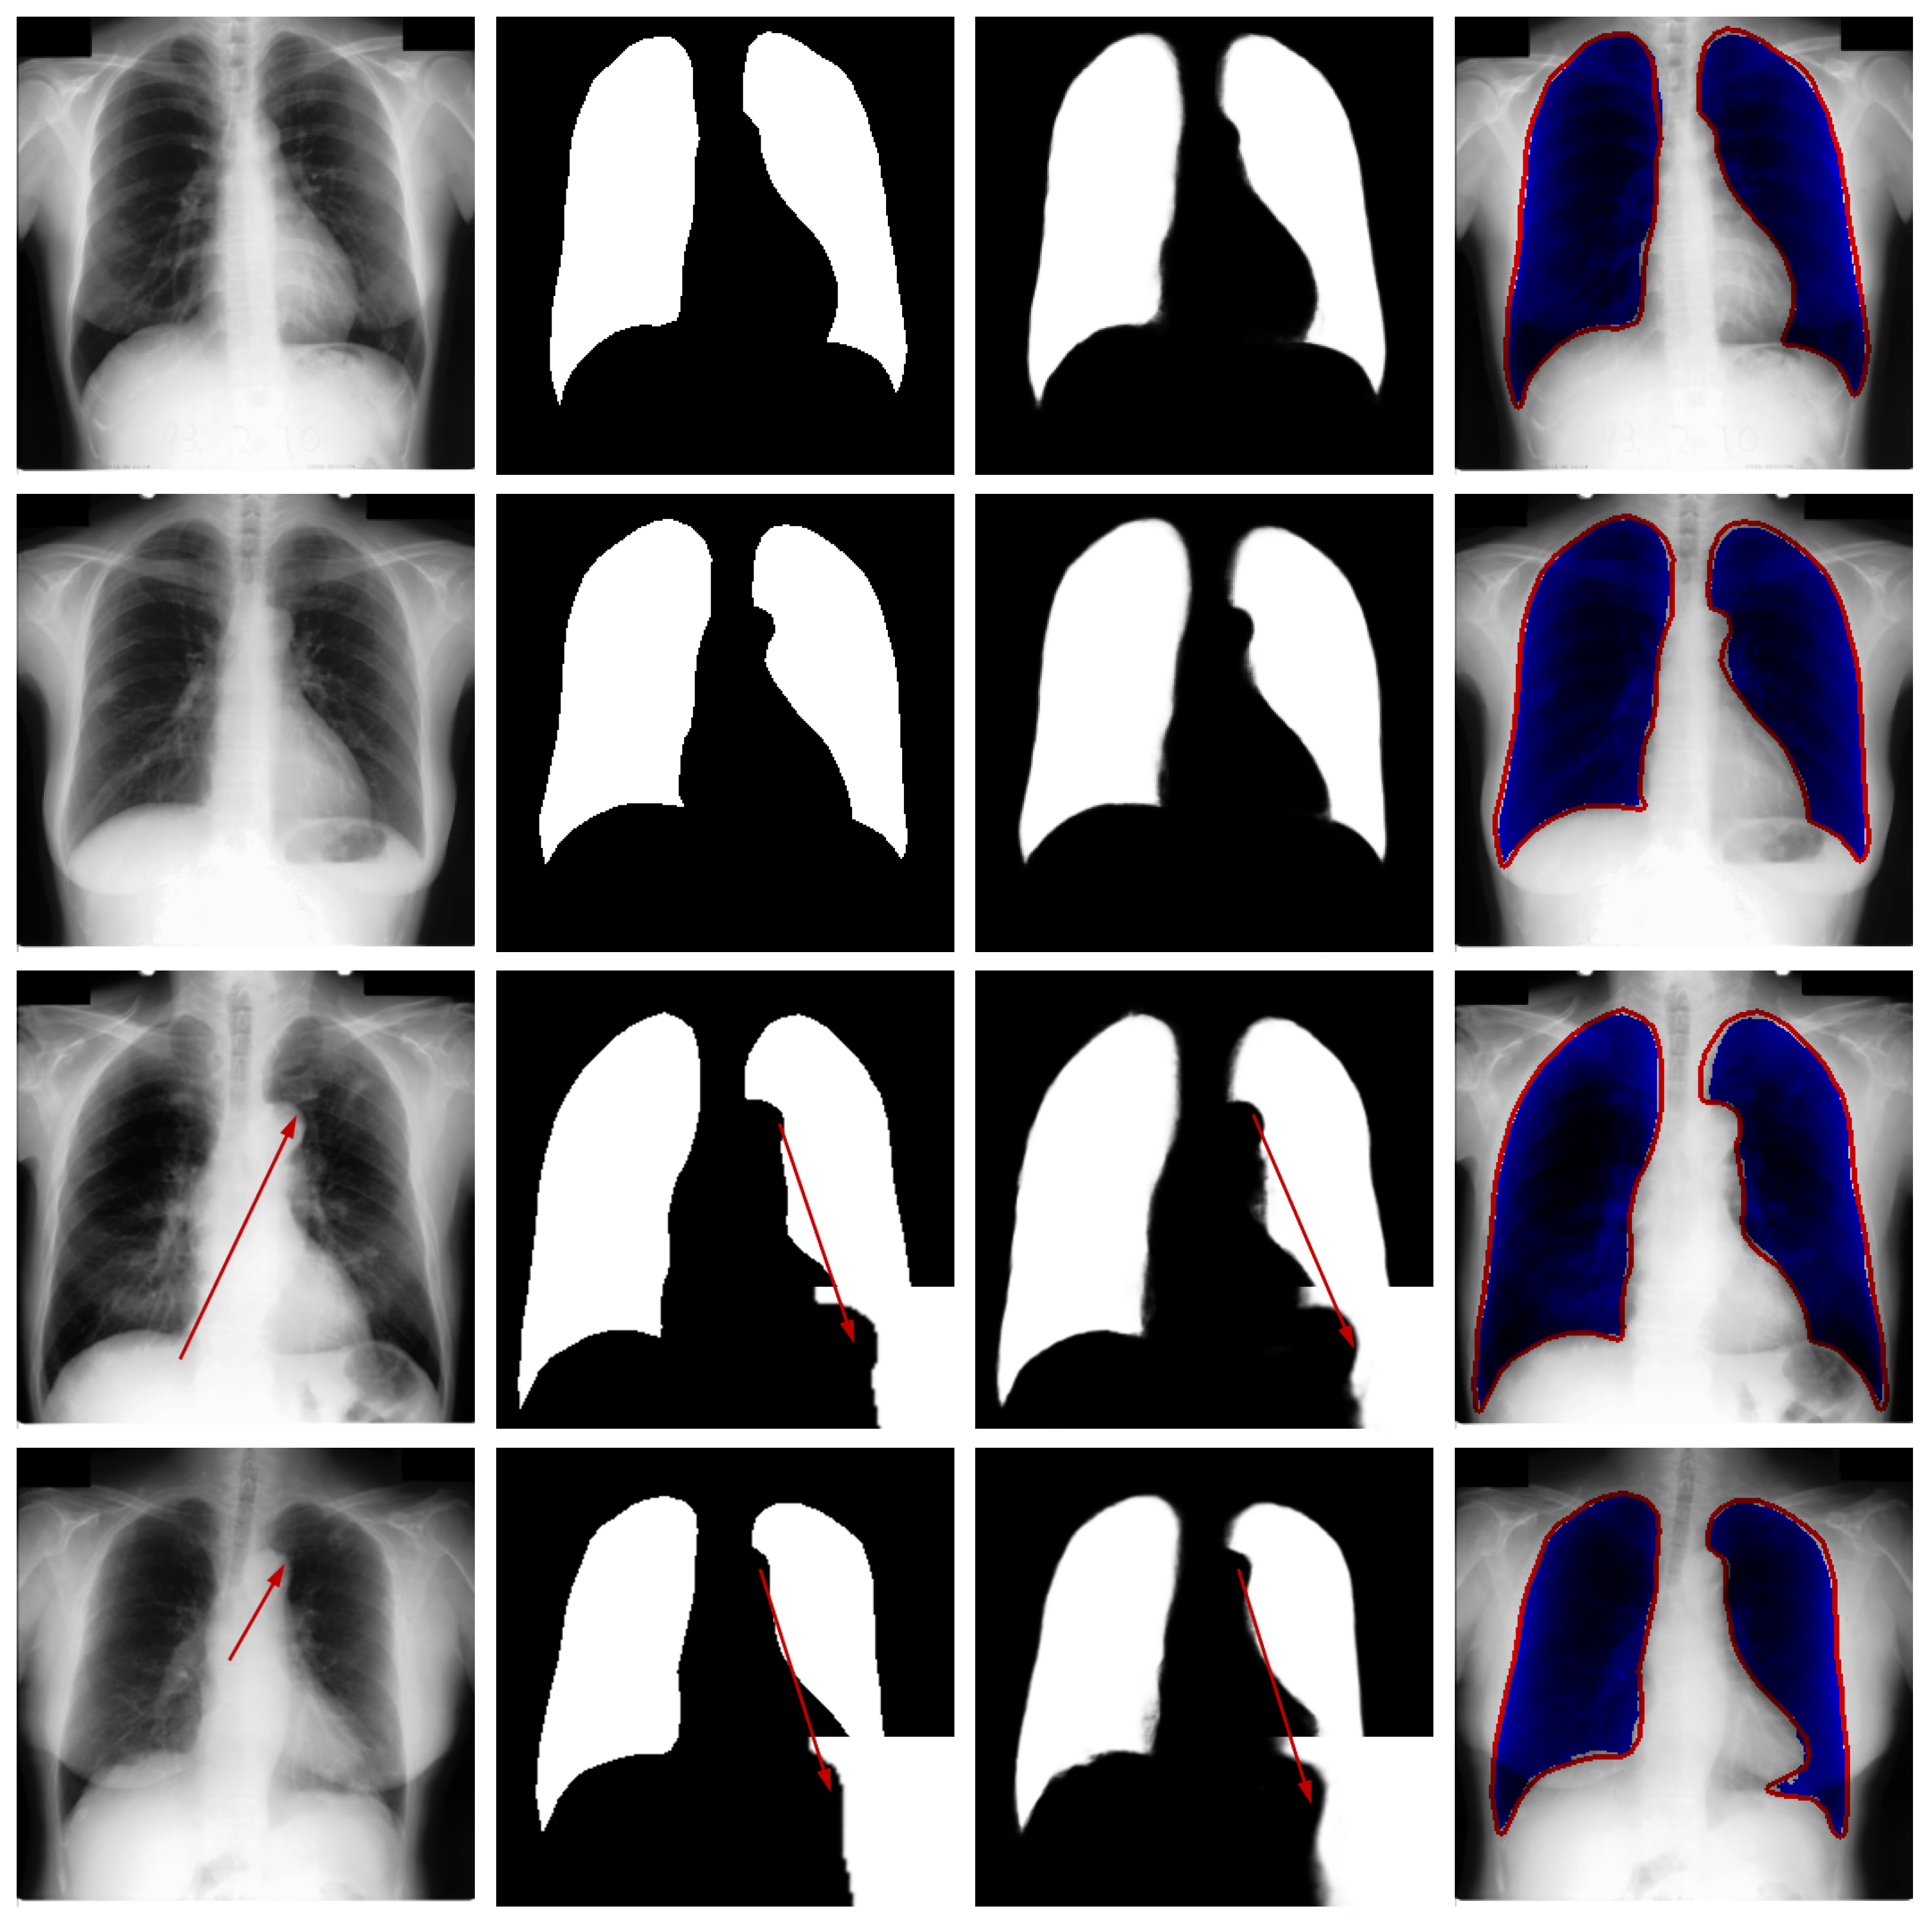

Qualitative Analysis: Figure 5 illustrates the segmentation outputs for the Montgomery County X-ray dataset. Visual examination reveals strong agreement between the model’s predictions and the reference annotations. The model successfully navigates these complexities, accurately separating the lung fields from the mediastinum and the diaphragm, as evidenced by the clean segmentation boundaries in the third column. Crucially, as highlighted in the third and fourth rows of Figure 5, the network maintains high precision even in regions where the contrast between lung tissue and the surrounding pleura is very low. The difference maps show only sporadic and minor errors, primarily in the costophrenic angles where boundaries are inherently faint, confirming the model’s high operational reliability for clinical X-ray imaging.

Figure 5.

Sample results from the testing set. From left to right: original image, ground truth, predicted segmentation mask, and the difference map. The red arrows in the third and fourth rows of the first column in the figure represent difficult recognition areas, the red arrows in the second column represent corresponding ground truth image edge areas, and the red arrows in the third column represent difficult recognition edges in the predicted image. The blue area in the fourth column represents the predicted areas, and the red part represents the ground truth contour.